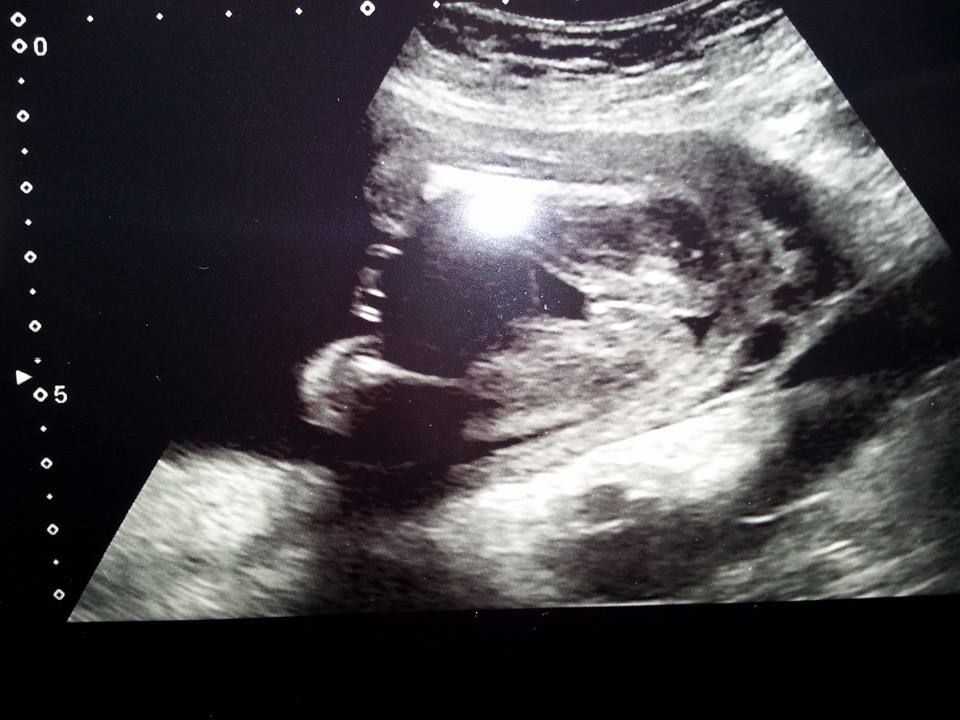

Attachment 15782 Double Checking :)

Looks like girl parts to me!